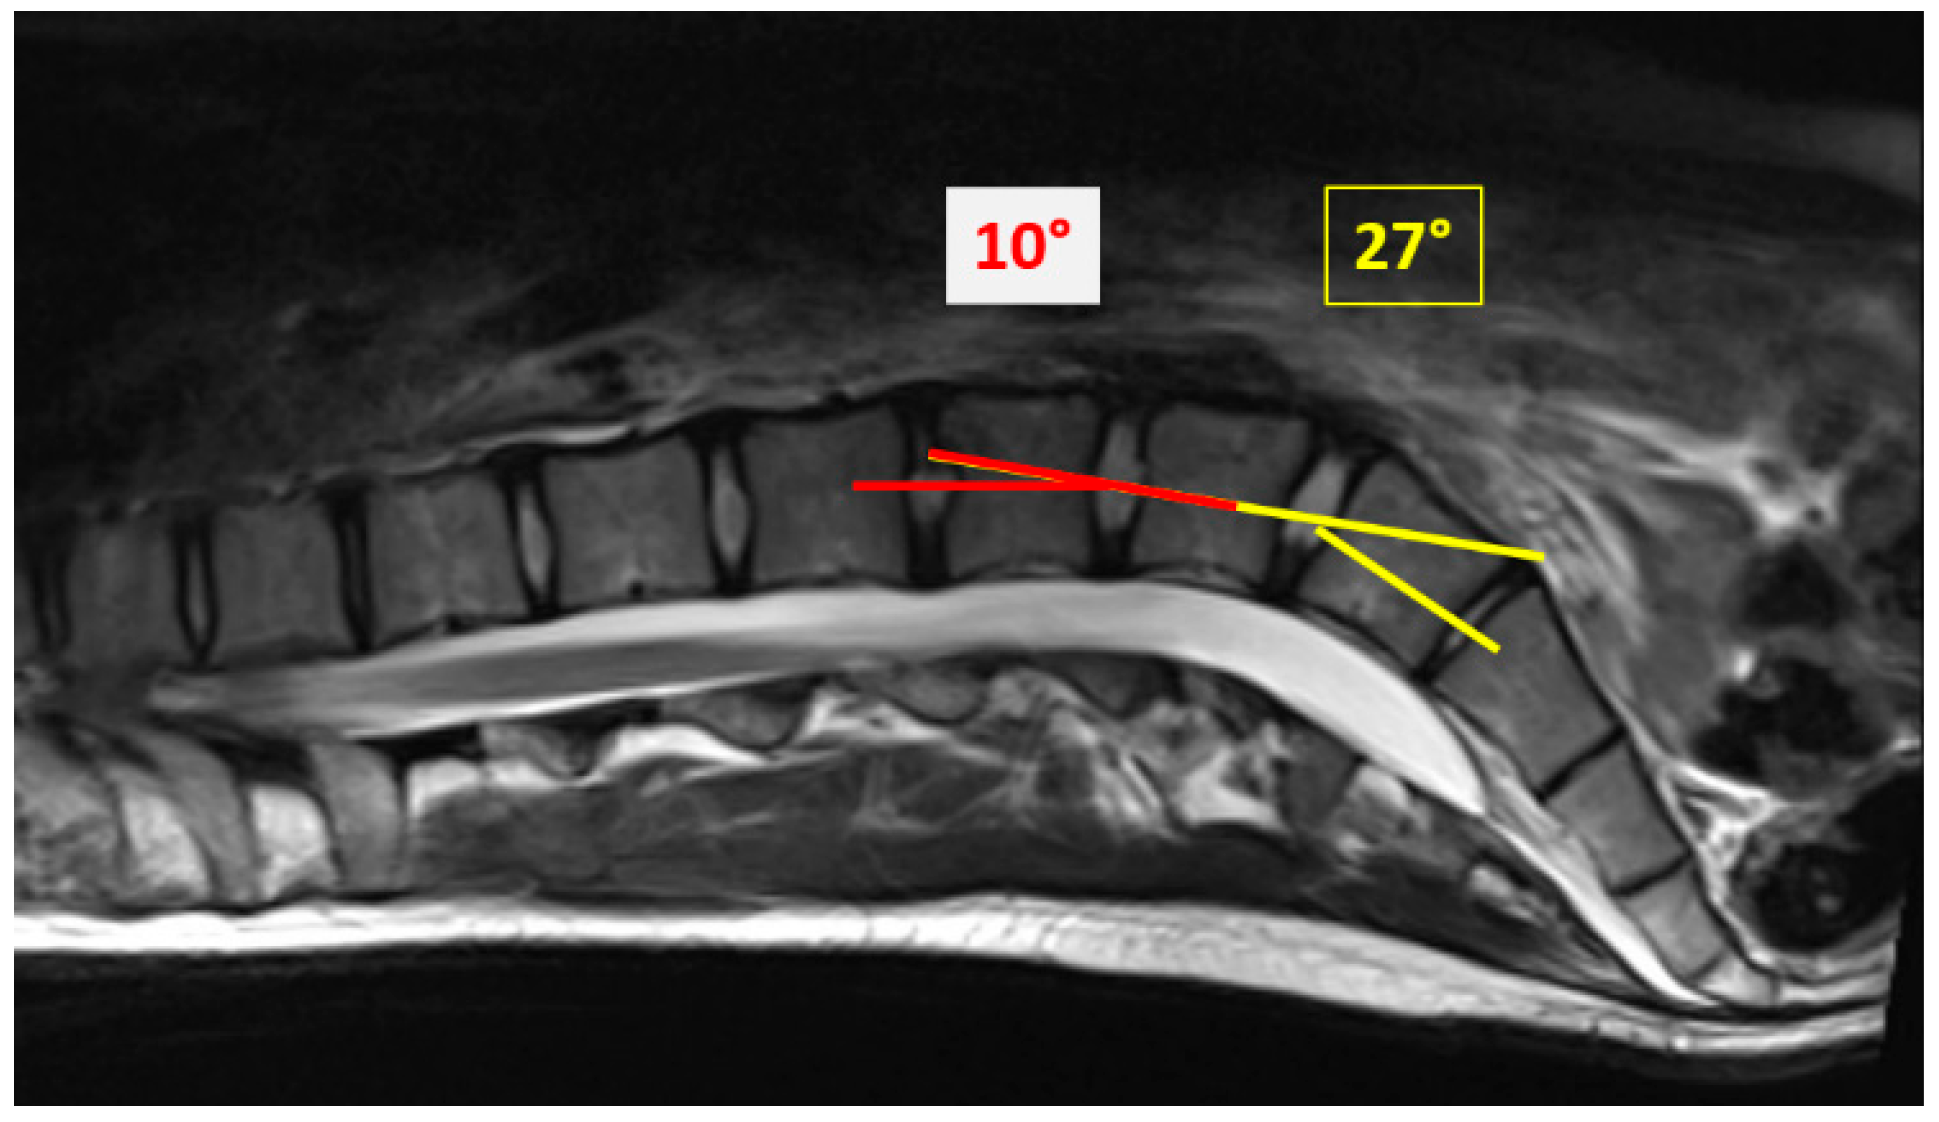

3.4. VMVM Vertical Mid-Vertebral Angle and Diff-VMVA in the Lowest Vertebral Segments

| Vertical Mid-Vertebral Angle | |||

|---|---|---|---|

| VMVA S1-L5 | 30.2° | n-72 | |

| VMVA L5-L4 | 18.8° | n-72 | |

| Diff-VMVA | 11.5° | n-72 | |

| Castellvi Classification | |||

| IIA | Diff-VMVA | 12.4° | n-54 |

| IIB | |||

| IIIA | Diff-VMVA | 9.3° | n-16 |

| IIIB | |||

| IV | Diff-VMVA | 5.5° | n-2 |